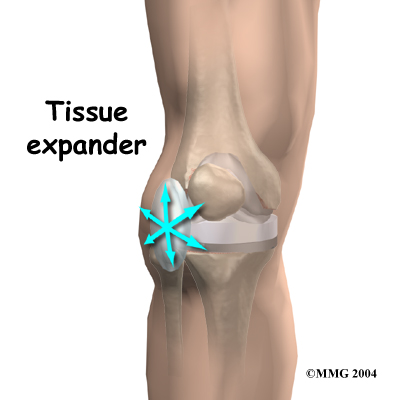

Past incisions in the knee can further complicate the planned revision procedure. People needing a knee revision will have at least one previous knee incision. Most surgeons who do knee revision surgery prefer to make an incision that runs down the center of the knee. This may not be possible due to previous knee incisions. The second choice is usually toward the outer (lateral) side of the knee. (Lateral is the side furthest from your other knee.) If the skin appears to be too tight for a planned incision to close, the risk of wound complications is high after the revision procedure. The orthopedic surgeon may need to consult with a plastic surgeon to ensure the best approach and result.

Another option is to use . These are placed just under the skin next to where the revision incision will eventually go. The expanders stay in for up to eight weeks and are removed when you go in for the revision surgery. The idea is that the skin will have stretched enough so that, when the revision procedure is done, the edges of the skin can be closed and sutured together.

Another option is to use . These are placed just under the skin next to where the revision incision will eventually go. The expanders stay in for up to eight weeks and are removed when you go in for the revision surgery. The idea is that the skin will have stretched enough so that, when the revision procedure is done, the edges of the skin can be closed and sutured together.

If your surgeon suspects that the artificial knee is loose, other tests may be necessary to find out why the joint is loose. Before any plans are made to revise the artificial joint, most orthopedic surgeons will want to make sure that the knee is not loose because of infection. To check for infection, blood tests may be ordered. Your surgeon may also need to  Another option is to use

Another option is to use